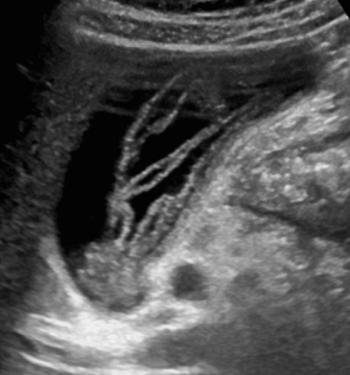

US finding

- 담관과 연결되는 많은 낭포가 있다.

- 담관 내 결석과 반사체가 보인다.